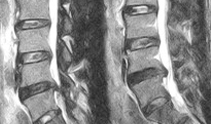

起坐骨神經痛 的原因頗多,最常見的病因 之一是腰椎間盤向後突出,造成神經根的直接壓迫,此症狀即稱椎間盤突出症。椎間盤---是 連接兩椎體之間的盤狀纖維軟骨結構, 使脊椎可以在相當的角度之間活動, 有如避震器的功能。腰椎有五個椎間盤, 是下半脊椎主要的活動關節。 腰椎橫剖即可見椎間盤主要是由周圍的纖維環及中央的髓核組成。 纖維環是數十層環狀及放射狀的膠原纖維及彈性纖維交織而成的緻密組織,將各椎體緊密的連接成一體,由於纖維具彈性使脊柱有相當的活動空間。髓核是白色半流質的膠狀物質, 填充於上下軟骨板及纖維環之間, 是由極具黏彈性及柔韌的多醣體和水分所組成,可以如緩衝脊柱的 . . .